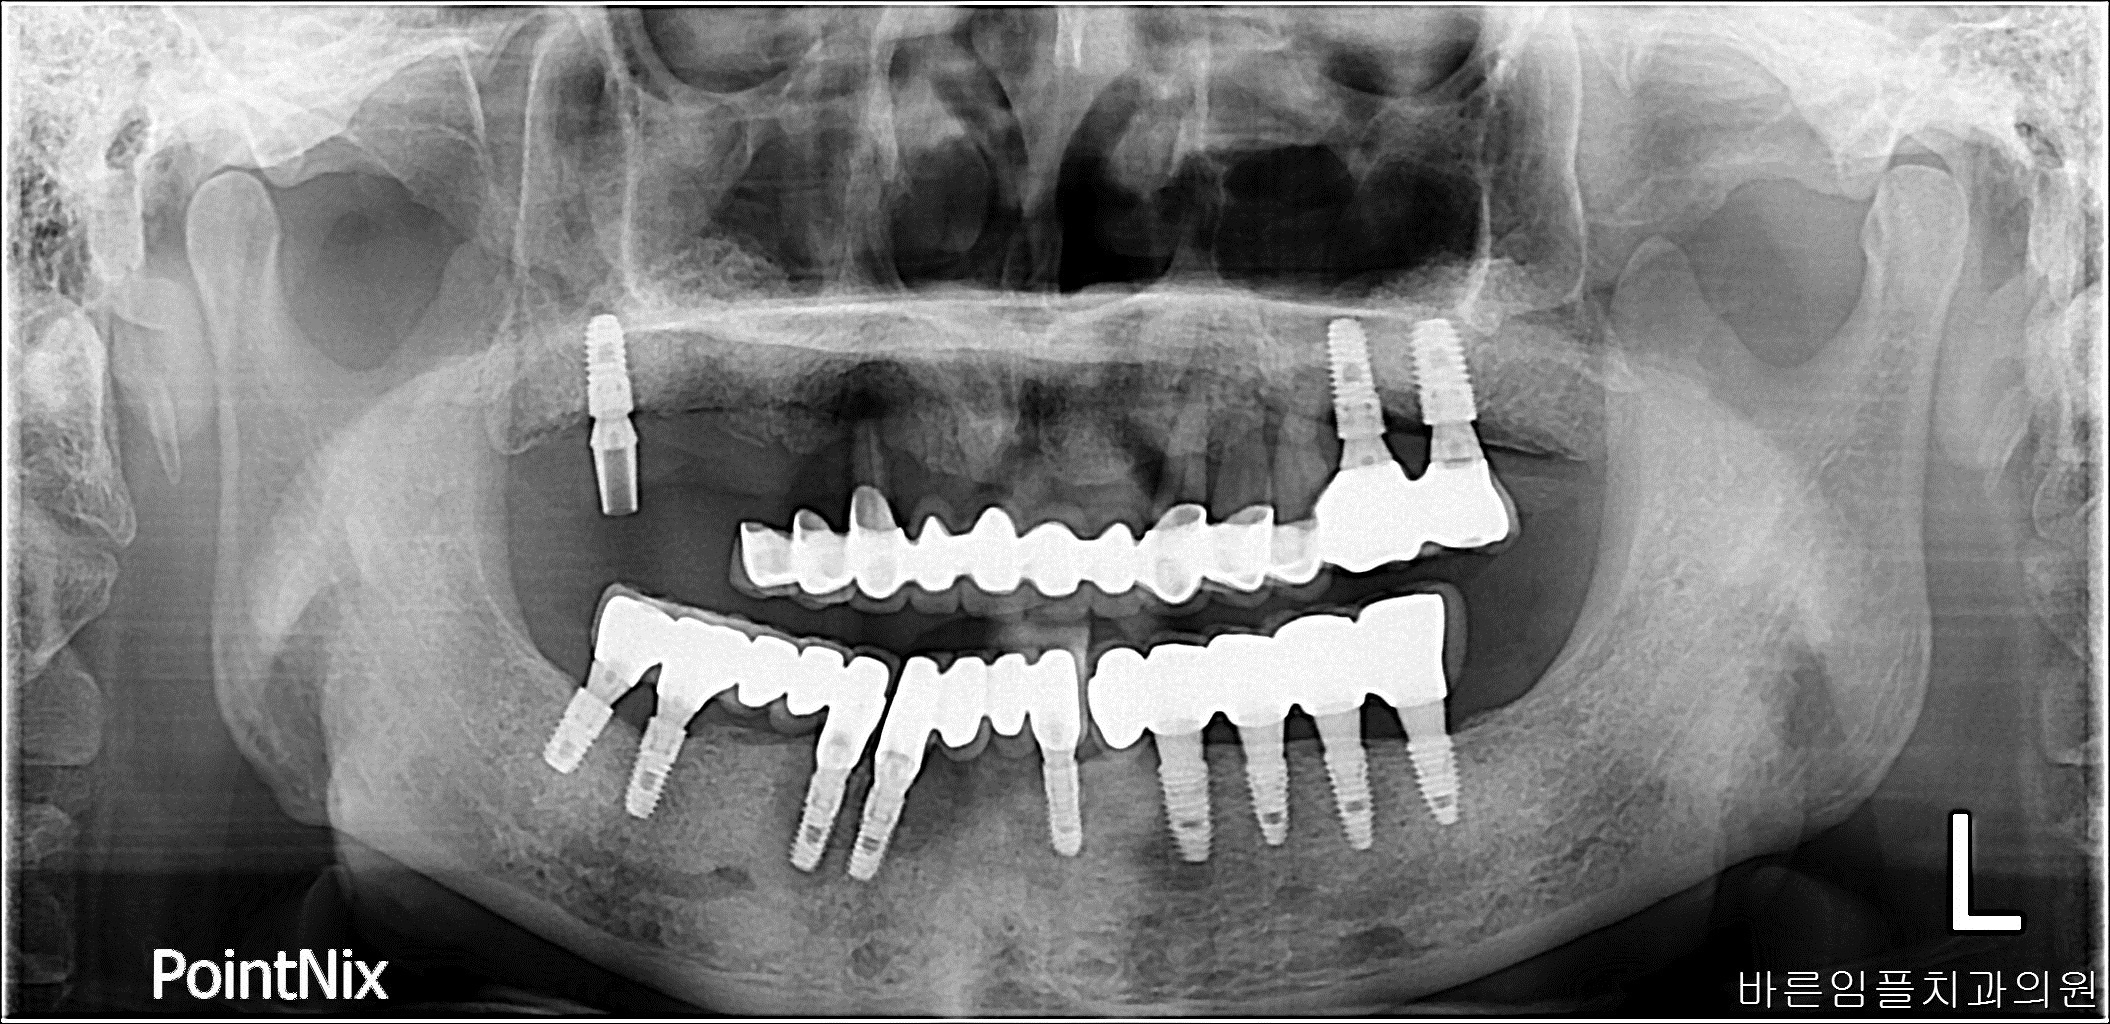

김ㅇㅇ / 수면임플란트 페이지 정보 작성일 23-10-27 17:01 2022-10-26 김ㅇㅇ Before 2023-09-02 김ㅇㅇ After 김ㅇㅇ / 수면임플란트 목록 이전글남ㅇㅇ / 임플란트 다음글 김ㅇㅇ / 임플란트